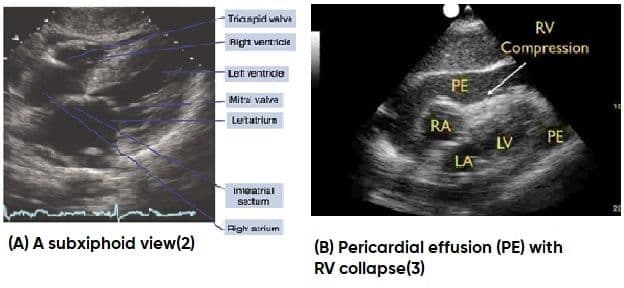

A patient with a suspected cardiac injury should be evaluated in an organized and expeditious manner, focusing on the primary survey. ABCDEs involve assessment of the airway, breathing, circulation (including obtaining vascular access), disability (Glasgow coma scale), environment, and exposure. As part of the survey a FAST examination should be performed. FAST is sensitive at identifying fluid within the pericardial sac, which can be concerning for hemopericardium in the setting of trauma (Figure 1). To obtain the subxiphoid view, the transducer is placed in the subxiphoid position pointing towards the heart with the transducer notch to the left side of the patient. This will allow evaluation for fluid around the heart. One may consider downloading a freely available application such as “FAST Heart,” which can be used as a bedside assistant to validate appropriate views and aid in diagnosis of common pathologies.